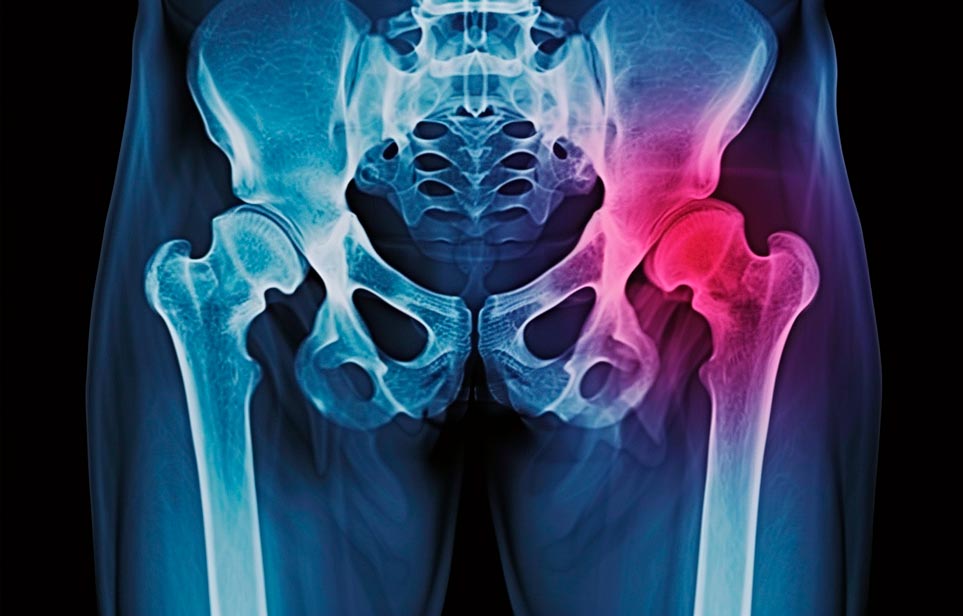

Реабилитация пожилых после перелома шейки бедра в Омске

Эффективная и профессиональная реабилитация после перелома шейки бедра в Омске осуществляется по демократичным ценам лучшими специалистами современной медицинской клиники «Заботливые люди» с применением персонального подхода к каждому пожилому человеку с такой тяжёлой травмой бедренной кости ноги. В процессе осуществления такой специализированной услуги все наши пациенты имеют возможность получения качественного и достойного обслуживания, эффективного восстановления. Лучший дом престарелых позаботиться о Вашем близком человеке.

Такая травма в большей части случаев возникает у граждан преклонного возраста. При её появлении на протяжении длительного времени сохраняются болевые и неприятные ощущения в области паха, при которых серьёзно ухудшается качество жизни, возникает множество последствий для его жизни и здоровья.

По какой симптоматике можно определить перелом шейки бедра

- Визуально повреждённая нога сокращается на несколько сантиметром из-за сокращения мышц.

- Стопа выворачивается наружу.

- В лежачем положении человек не может поднять ногу.

При такой симптоматике важно незамедлительно обращаться к специалистам для получения всей необходимой помощи, терапии и восстановления после перелома шейки бедра. Если не оказать помощи старику, то это приведёт к гноению, инвалидности, иным видам осложнений.